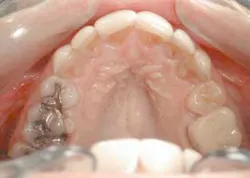

With our patient, this evaluation reveals the centrals to be approximately 8.5 mm wide and 9.5 mm long. (Fig. 3) This would make the existing W/L ratio 89 percent. The Golden Proportion evaluation shows that the centrals appear too wide and we see too much of the canines.